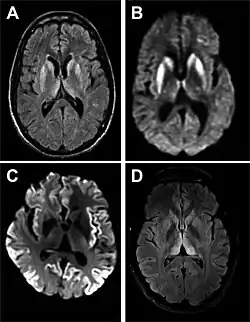

Magnetresonanztomographie

Bei der Diagnose ist die Magnetresonanztomographie die bildgebende Untersuchung der Wahl bei klinisch vermuteten nvCJD. Typisch sind Signalerhöhungen in FLAIR-Bildern (fluid-attenuated inversion recovery) und in diffusionsgewichteten Aufnahmen, vermutlich durch den spongiösen Strukturverlust.[14] In über 90 % der neuropathologisch bestätigten nvCJD-Fälle zeigte sich schon in frühen Stadien der Erkrankung (2 bis 10 Monate nach Beginn der Symptome) im Thalamus das sogenannte Pulvinarzeichen. Dies ermögliche in den meisten Fällen die Diagnose, ohne dass weitere Untersuchungen erforderlich seien.[15]